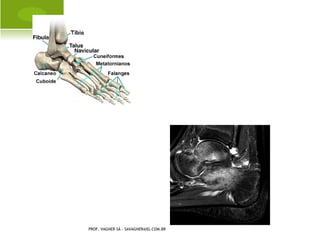

A NOMALIAS CONGÊNITAS DOS

MEMBROS INFERIORES

P É E QUINOVARO

P É TORTO C ONGÊNITO

T ÁLUS I NVERTIDO